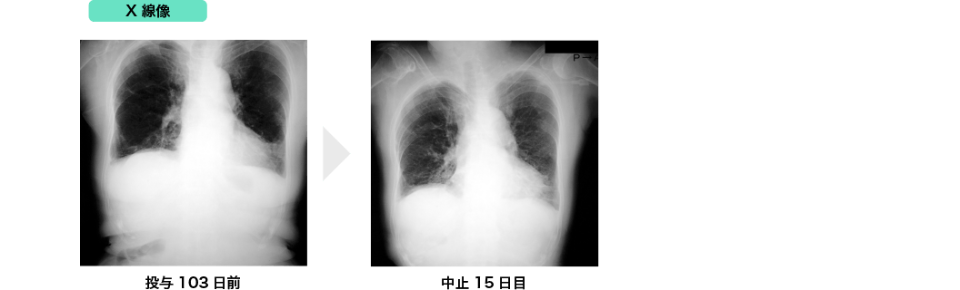

参考症例

(1) 間質性肺炎発現症例